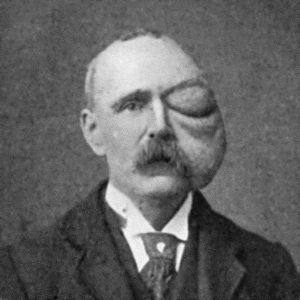

Fig. 1.—Ulcer of back of Hand covered by flap of skin raised from anterior abdominal wall. The lateral edges of the flap are divided after the graft has adhered.

Another modification is to raise the flap but leave it connected at both ends like the piers of a bridge; this method is well suited to defects of skin on the dorsum of the fingers, hand and forearm, the bridge of skin is raised from the abdominal wall and the hand is passed beneath it and securely fixed in position; after an interval of 14 to 21 days, when the flap is assured of its blood supply, the piers of the bridge are divided (Fig. 1). With undermining it is usually easy to bring the edges of the gap in the abdominal wall together, even in children; the skin flap on the dorsum of the hand appears rather thick and prominent—almost like the pad of a boxing-glove—for some time, but the restoration of function in the capacity to flex the fingers is gratifying in the extreme.

Fig. 1.—Ulcer of back of Hand covered by flap of skin raised from anterior abdominal wall. The lateral edges of the flap are divided after the graft has adhered.